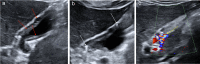

Gallbladder polyps are protuberances of the gallbladder wall projecting into the lumen. They are usually incidentally found during abdominal sonography or diagnosed on histopathology of a surgery specimen, with an estimated prevalence of up to 9.5% of patients. Gallbladder polyps are not mobile and do not demonstrate posterior acoustic shadowing; they may be sessile or pedunculated. Gallbladder polyps may be divided into pseudopolyps and true polyps. Pseudopolyps are benign and include cholesterolosis, cholesterinic polyps, inflammatory polyps, and localised adenomyomatosis. True gallbladder polyps can be benign or malignant. Benign polyps are most commonly adenomas, while malignant polyps are adenocarcinomas and metastases. There are also rare types of benign and malignant true gallbladder polyps, including mesenchymal tumours and lymphomas. Ultrasound is the first-choice imaging method for the diagnosis of gallbladder polyps, representing an indispensable tool for ensuring appropriate management. It enables limitation of secondary level investigations and avoidance of unnecessary cholecystectomies.